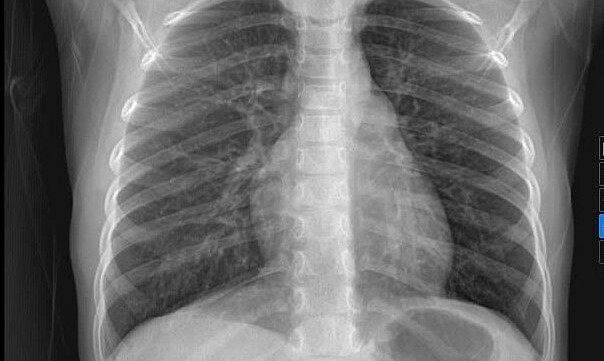

Bệnh nhi được chụp X-quang ngực để tầm soát ổ nhiễm trùng. Ảnh: Bệnh viện Đa khoa Tâm Anh

Ngày 22/1, BS.CKI Nguyễn Hữu Hiếu, khoa Nhi, Bệnh viện Đa khoa Tâm Anh TP HCM, cho biết các triệu chứng của bệnh nhi dễ bị nhầm lẫn với tình trạng viêm mũi họng thông thường. Bệnh nhi được siêu âm bụng, siêu âm thóp, chụp X-quang ngực để tầm soát ổ nhiễm trùng nhưng kết quả không ghi nhận bất thường.